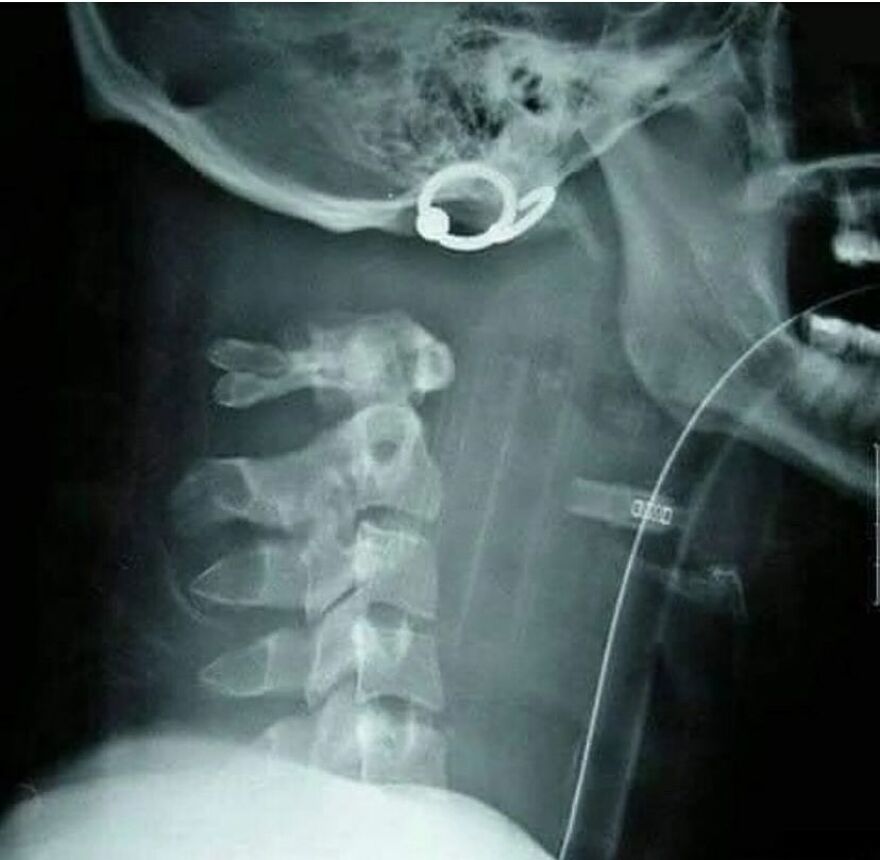

Anterior cervical discectomy and fusion

“Anterior cervical discectomy and fusion (ACDF) is a surgery to remove a herniated or degenerative disc in the neck. An incision is made in the throat area to reach and remove the disc. A graft is inserted to fuse together the bones above and below the disc.“